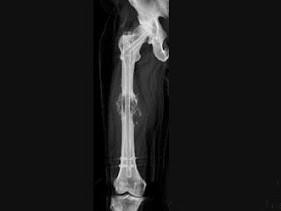

问题 男,18岁,右股骨肿瘤术后,现大腿中部疼痛、肿胀,夜间尤甚,结合CT图像,最可能的诊断是 ( )

选项 A、成骨性骨转移瘤 B、化脓性骨髓炎 C、Ewing肉瘤 D、骨肉瘤 E、骨纤维肉瘤

答案 D